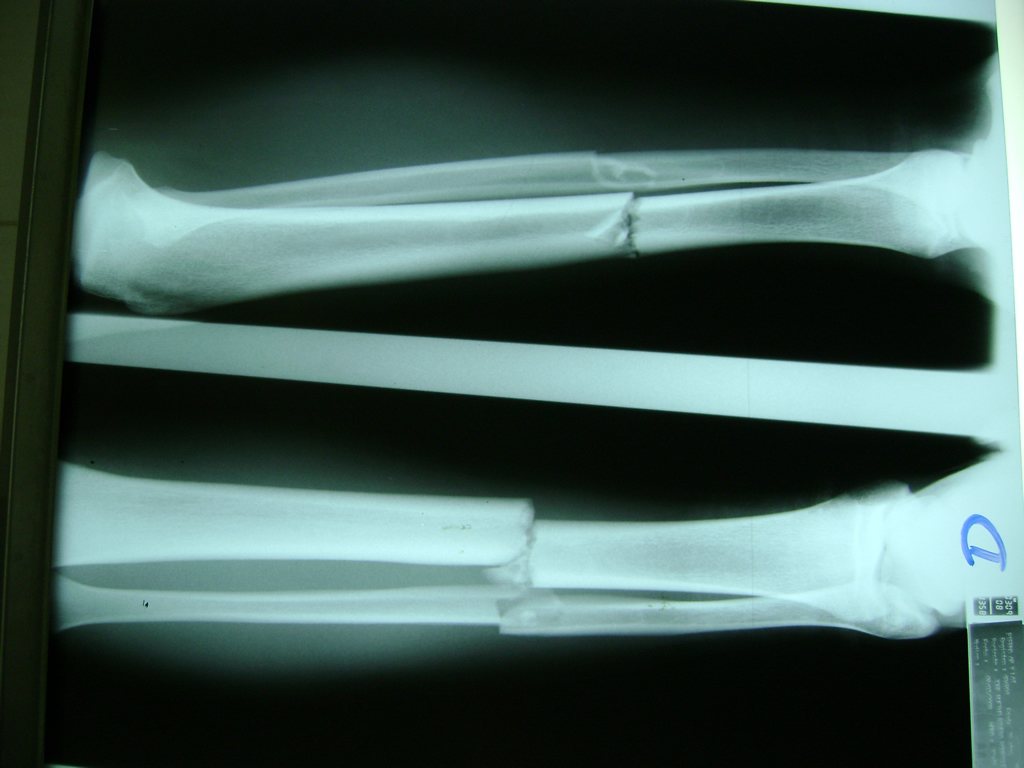

Cirugías de Calcaneo - Perone y Tibia

Aunque cada uno de estos huesos puede fracturarse por separado, normalmente la rotura es una lesión que se produce de forma conjunta

La mayor parte de las roturas implican a la parte proximal del hueso (parte del hueso próximo a la rodilla) o a la parte distal (parte del hueso cerca del tobillo).

Debido a la fina cobertura de piel que recubre la tibia y el peroné, las fracturas generalmente son abiertas, es decir, el hueso roto rasga la piel, atravesándola. Las fracturas de tibia y peroné generalmente se producen por un fuerte impacto o torsión.